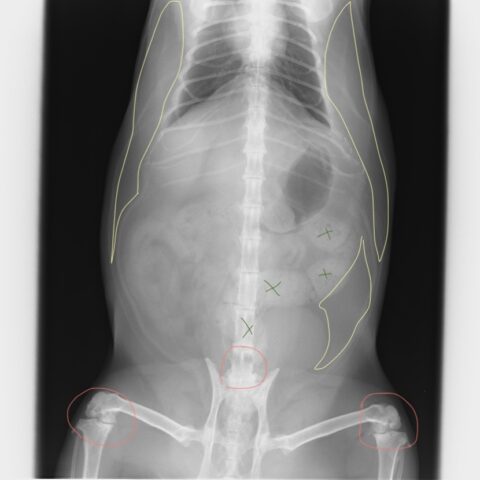

レントゲンの所見

黄色い線の囲み :脂肪・・・内蔵脂肪が多い 肋骨脇から腹部の皮下脂肪が多く胸郭を圧迫している

オレンジの線の囲み :腰椎の変形性脊椎症と膝関節の変形性関節症

緑の✗印 :便秘の便